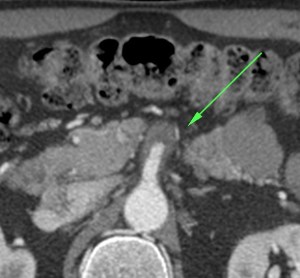

Flecha roja: colateral que repermeabiliza la AMS.

Se realiza TC de abdomen en vacío y con contraste en fase portal:

Estamos ante un cuadro de isquemia intestinal en un paciente con bajo gasto cardiaco con afectación principal de asas intestino delgado, territorio vacularizado por la arteria mesentérica superior.